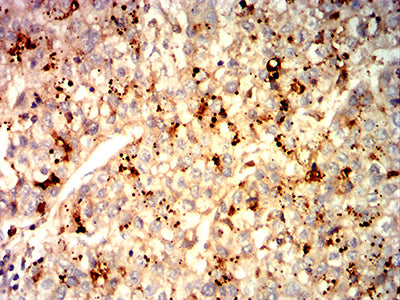

分类: 科研抗体货号: 31967别名: NK1; CD57; HNK1; LEU7; NK-1; GLCATP; GLCUATP应用: IHC,FCM反应种属: Human